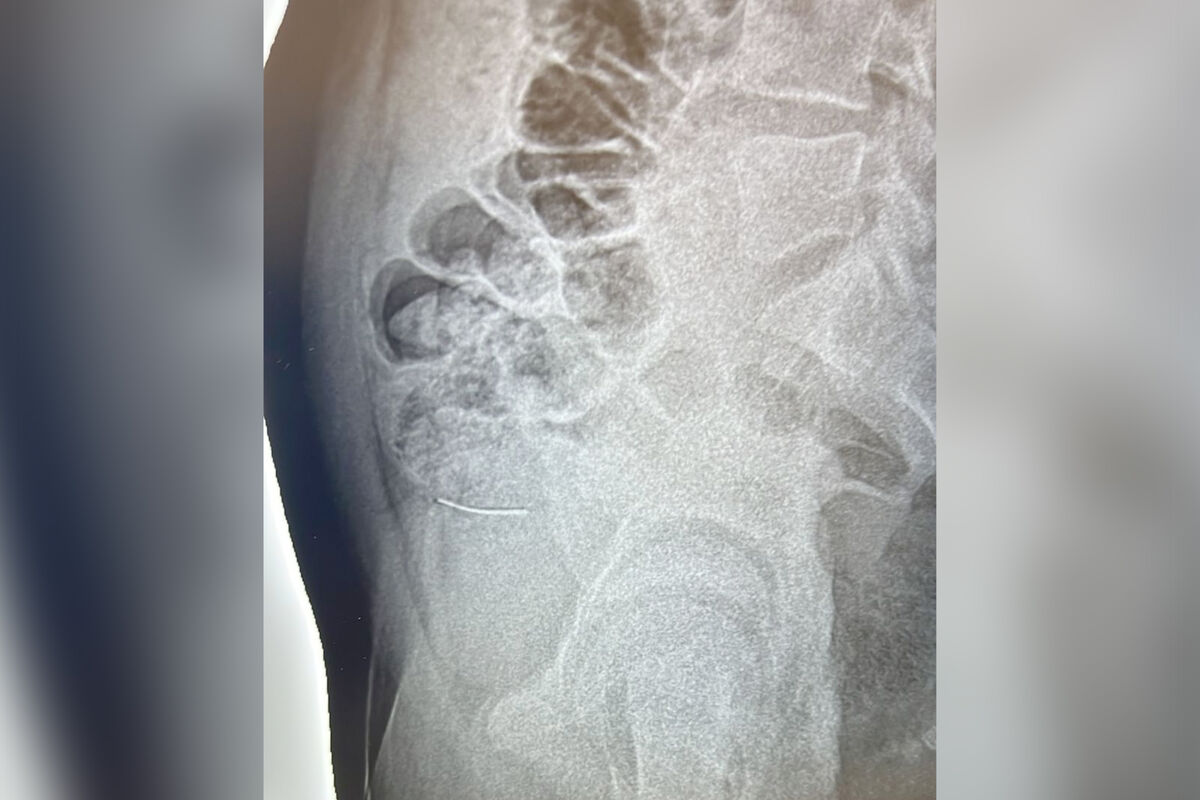

Обследование подтвердило слова мальчика — рентген показал наличие инородного предмета в подвздошной кишке.

«Больной был прооперирован: проведена лапаротомия, ревизия брюшной полости, удаление инородного тела подвздошной кишки, ушивание перфорации подвздошной кишки; санация и дренирование брюшной полости», — рассказали врачи, добавив, что постоперационный период прошел без осложнений.